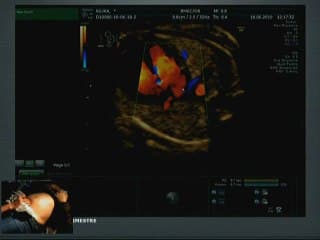

La médiathèque du Collège Français d'Échographie Fœtale (CFEF) constitue l'une des plus importantes collections de ressources vidéo dédiées à l'échographie fœtale en France. Avec plus de 3 261 vidéos, elle couvre l'ensemble des thématiques liées à la pratique échographique prénatale.

Vous y trouverez des conférences présentées lors des congrès nationaux et internationaux, des cours magistraux dispensés par des experts reconnus, des démonstrations pratiques sur des cas cliniques réels, ainsi que des podcasts et tables rondes sur les dernières avancées de la spécialité.